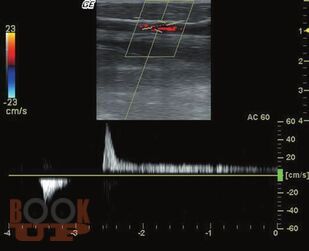

Ультразвуковое исследование вен нижних конечностей: анатомия, рефлюксы, тромбозы и хирургические подходы

Когда врач решает освоить ультразвуковое исследование вен нижних конечностей, первое, с чем он сталкивается - вен там очень много и в них легко запутаться. Кроме этого, в венах есть правильное направление течения крови, а есть неправильное - рефлюкс, и его нужно уметь правильно определять в нужных местах. Кроме рефлюксов, в венах встречается более опасное заболевание - тромбоз. Очень важно понять, где ситуация критическая и с найденным тромбом нужно срочно что-то делать, а где - ничего страшного, больному можно улыбнуться и сказать: «пройдет само». Кроме этого, в венах (в отличие от артерий) очень выражена индивидуальная изменчивость, нет понятия «нормальных» размеров и «гемодинамически значимого стеноза».